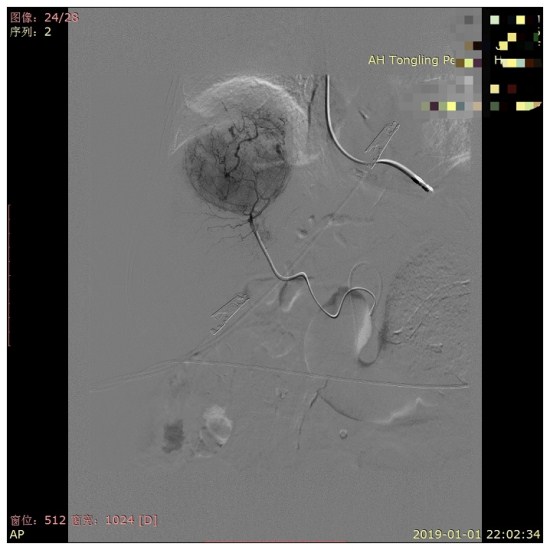

1月1日晚上8点,120救护车将一名93岁高龄的女性患者紧急送至我院急诊抢救部。入院时患者精神萎,躁动不安,脉氧78%,心率127次/分,血压在多巴胺维持下也仅有65/48mmHg,完善相关检查后,考虑患者是“肝右叶巨块型恶性肿瘤伴出血;失血性休克”,病情十分危重,子女们非常着急!正值元旦假日,但放射科介入治疗团队接到电话急会诊后迅速到达抢救部,与急诊科、急诊外科、麻醉科等多学科紧急会诊。由于病人年高体弱,既往有糖尿病病史20余年,脑梗塞病史2年以及脑干出血病史1年等多种危重因素,手术切除肿瘤的风险极大,遂急诊先行全麻下超选择性肝动脉造影栓塞术以控制出血及缩小肿瘤。介入手术历时1小时,成功的将出血的肿瘤血管精准栓塞,术后患者转入重症医学科予以对症支持治疗,现患者已出院,正在康复中!